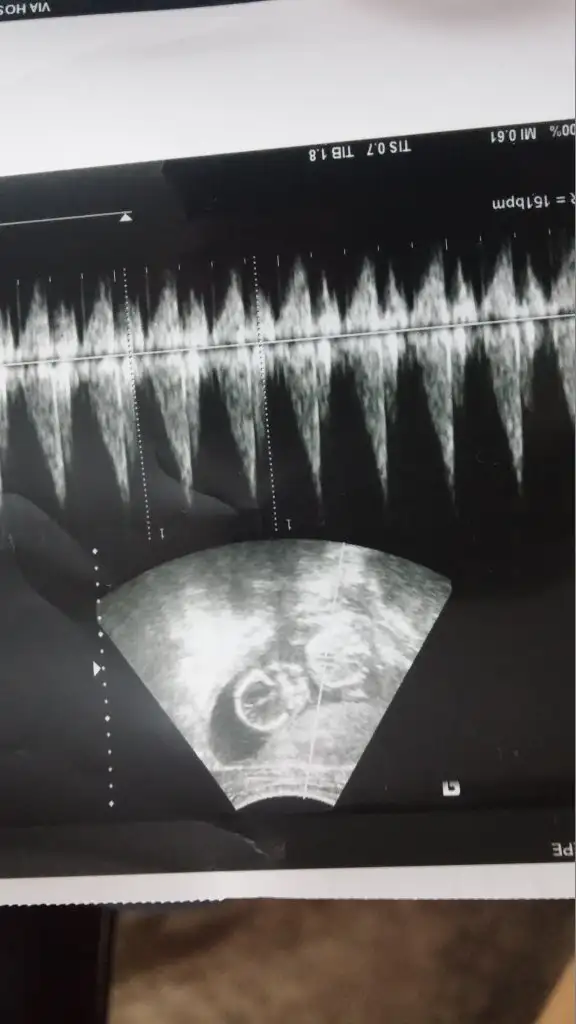

dr soylemeden siz gorun genital nub teorisi ( bebegin cinsiyeti)

kızlar banada yorumda blunabilirmisiniz ilk yolladığım 14 haftalık bunda doktor büyük olasılık erkek dedi 2. ci yolladığım ise 17 haftalık ama doktor minik çıkıntı var ama ben buna kız dicem dedi sizin görüşleriniz neler